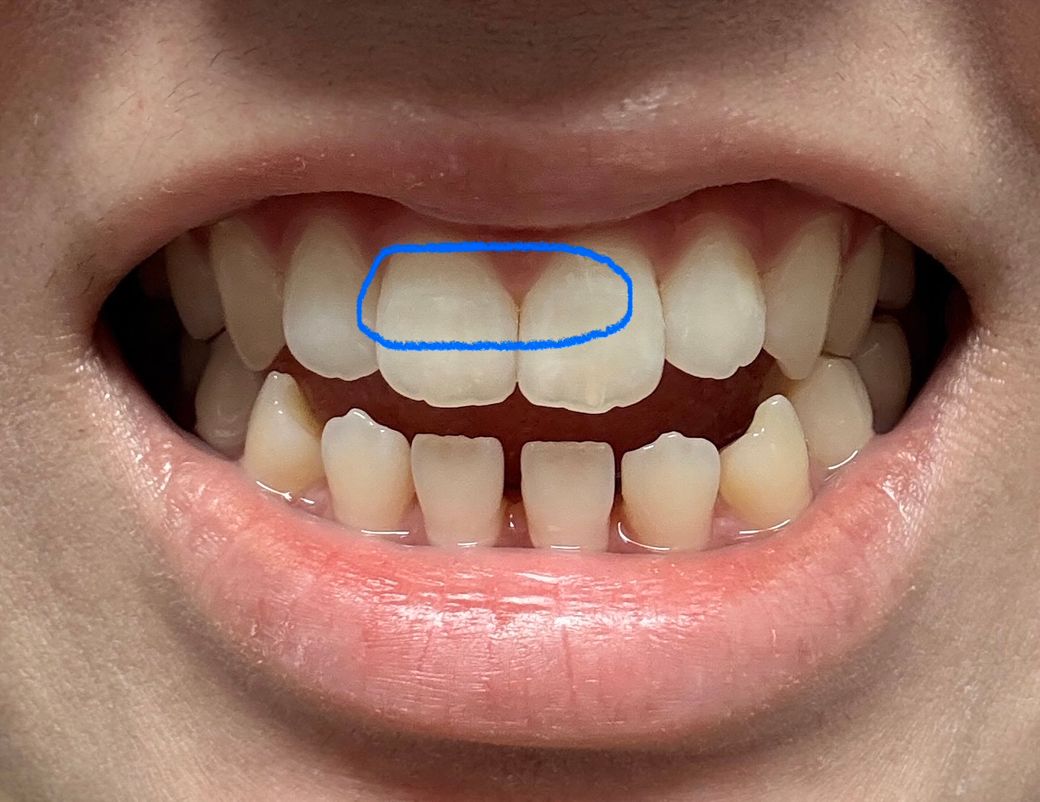

우연히 양치를 하나 봤는데 위 앞니양쪽 에 가로 금이 있더라구요 ㅠㅠ 특히 오른쪽이 좀더 진하구요(사진상은 반대에요) 그냥 외관상 봤을때는 첫번째 사진 파란 네모안에 처럼 좀 금이 살짝 보이는정도고 각도에 따라서 두번째 사진에 보라색 네모친 부분처럼 그림자처럼 보이기도해요 근데 확실히 플래쉬를 비추면 세번째 사진 초록색 네모부분안에 금이 훨씬 잘보여요 ㅠㅠ 혹시나해서 안쪽도 보니 금이 살짝있는데 바깥 금이랑은 같은 위치인지는 모르겠는데 네번째 사진상으로 안나와서 대충 그려서 올립니다! 검은 색 선처럼 약간 가로금이있어요 그런데 제가 원래부터 앞니에 세로로 된 실금은 좀 있었는데 가로로 된 실금은 처음봤어요 ㅠㅠ 그동안 앞니에 큰 충격은 따로 없었고 있어봤자 양치하다 칫솔에 앞니 부딪히는정도가 끝이었어요 몇주전 한번 금있는 치아가 갑자기 시리거나 물 닿았을때 시린건 한번씩 있었는데 그 뒤로는 불편한 건 없었고 금이 만져지거나 하지도않아요 그리고 무엇보다 이번년도 4월에 정기검진했는데 엑스레이도 촬영했는데 이때도 치아 금은 보이지않는다 그러셨거든요 ㅠㅠ 혹시몰라 마지막사진 첨부합니다 이때 금이 있었는지는 모르겠으나 이상없다하셨는데 외상이 없는데 갑자기 금이 생길수 있나요…? 제가 근데 개방교합이라 윗니들이 간격이 좁아서 살짝 튀어나오고 뒤틀어진건 있습니다 ㅠㅠ 일단 사진 보시기에 치료가 필요한 수준인가요..?😭 임플란트 해야할까봐 무서워요 ㅠㅠ 꼭 답변 부탁드릴게요..

• 1번 째 사진